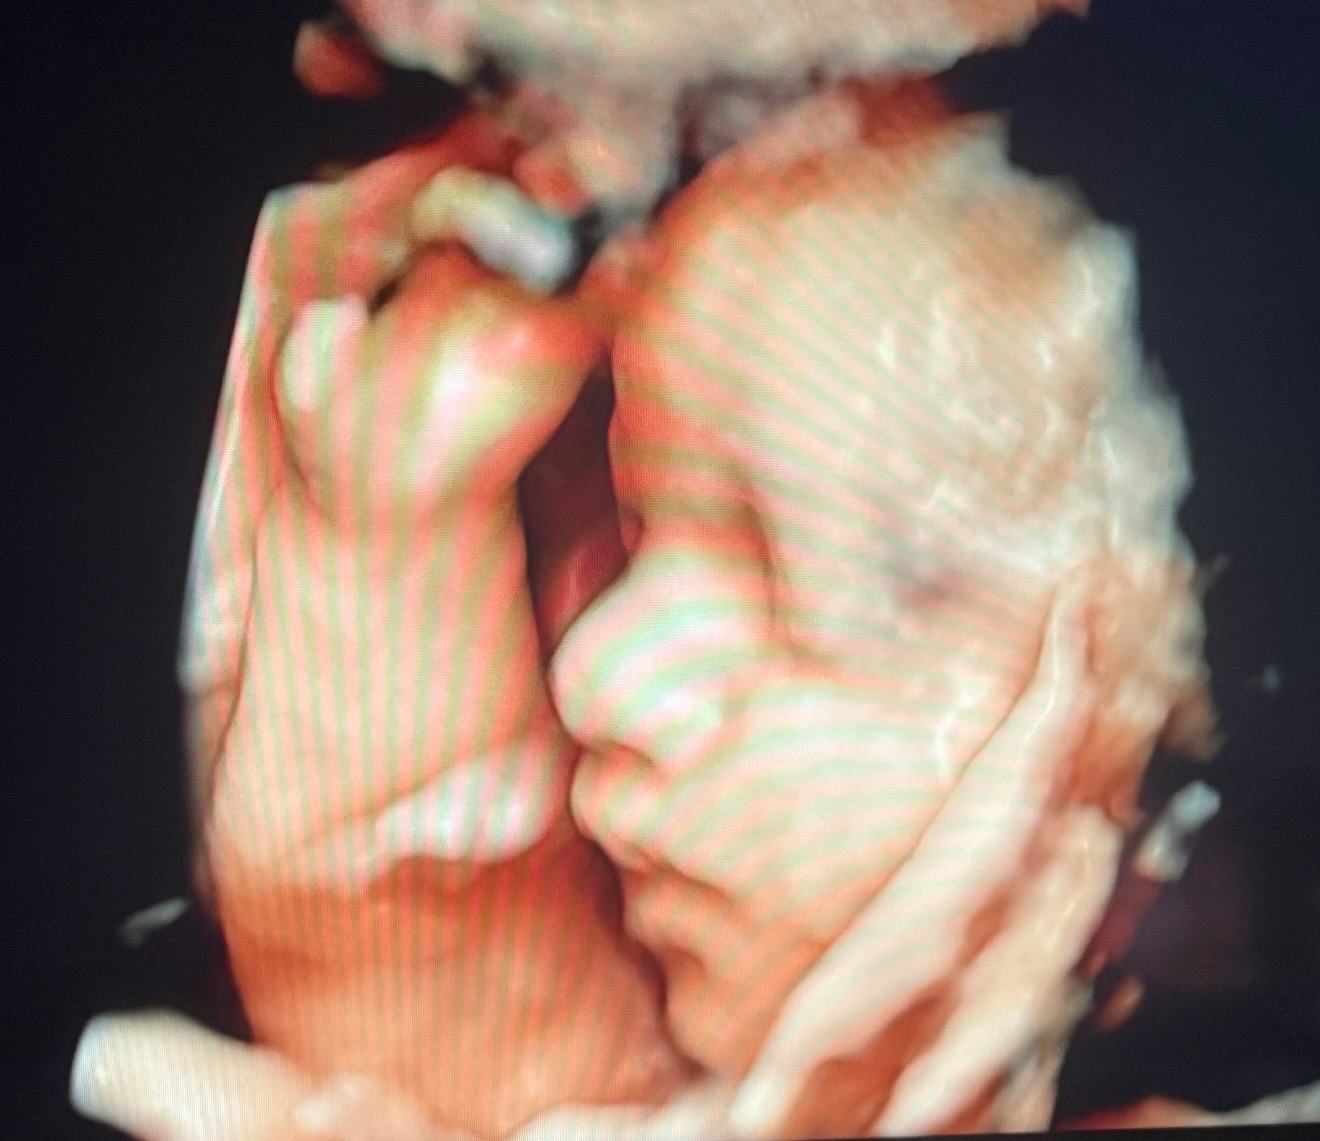

She and her husband, Edgar, are expecting their first child, sweet baby girl, Valentina. She is already so deeply loved, and we are trusting for strength, healing, and provision every step of the way. I created this GoFundMe to support them as they prepare for the medical care, surgeries, and unknowns ahead.

Valentina has been diagnosed with several complex congenital heart and organ conditions. She has Hypoplastic Right Heart Syndrome (HRHS), meaning the right side of her heart is underdeveloped. She also has Double Outlet Right Ventricle (DORV), where both major arteries come from the right side of her heart instead of being properly separated.

In addition, Valentina has Pulmonary Stenosis (PS), which means the pathway to her lungs is very narrow, making it harder for blood to flow properly.

She has also been diagnosed with heterotaxy syndrome, a condition that affects how her organs are arranged. Her stomach is on the right side, her liver sits in the middle, her intestines are rotated, and she does not have a spleen, which can affect her immune system.

Because of these conditions, Valentina will need at least two major heart surgeries, one around 3 months old and another around 3 years old, to help correct the “plumbing” of her heart and improve how it functions.

Immediately after birth, she will be transferred to the pediatric cardiac care unit at Children’s Hospital. There, doctors will perform genetic testing, an MRI, and evaluate whether her pulmonary veins are properly connected to her heart. Depending on what they find, she may need emergency surgery right after birth.